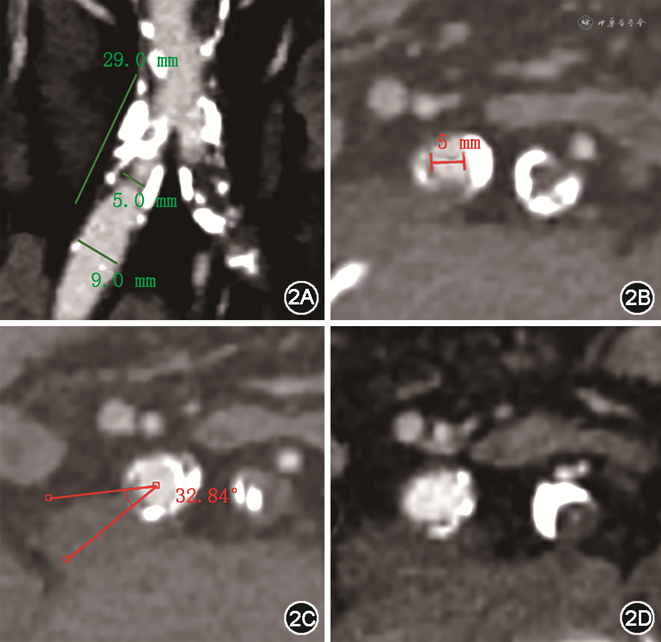

患者男性,67岁,因“反复活动后胸闷、气喘3个月余”于2022年10月7日入院。患者3个月来反复出现活动时胸闷、气喘,药物治疗效果不佳,症状逐渐加重。既往有高血压和糖尿病病史10余年。入院体格检查:血压110/68 mmHg(1 mmHg=0.133 kPa),心率80次/min,律齐,胸骨左缘3、4肋间可闻及4/6收缩期喷射样杂音。N末端B型利钠肽原1 336.0 ng/L(参考值0~100 ng/L),心肌酶、肌钙蛋白未见明显异常。超声心动图提示主动脉重度狭窄并轻度关闭不全(最大压差94 mmHg,平均压差53 mmHg,峰值流速4.84 m/s),左心室舒张期末径50 mm,左心室收缩期末径28 mm,左心室后壁厚度12 mm,射血分数73%,少量心包积液,左心室舒张功能减退。术前主动脉CT血管成像(CTA)提示功能性二叶瓣(Type Ⅰ型),瓣叶增厚,中度钙化,左右部分融合,左冠状动脉开口高约11.7 mm,右冠状动脉开口高约16.9 mm,法式窦结构可,窦管交界高约20.2 mm、直径约26.4 mm,心脏角度约52°,升主动脉未见明显扩张(图1)。术前髂动脉CTA提示双侧髂动脉走行迂曲。右髂总动脉近段弥漫性严重钙化,病变斑块长度>20 mm,右髂总动脉直径9 mm(图2A),最狭窄处直径5 mm(图2B),狭窄率接近70%,接近270°环形钙化(图2C)。左髂总动脉近段闭塞伴严重钙化(图2D)。